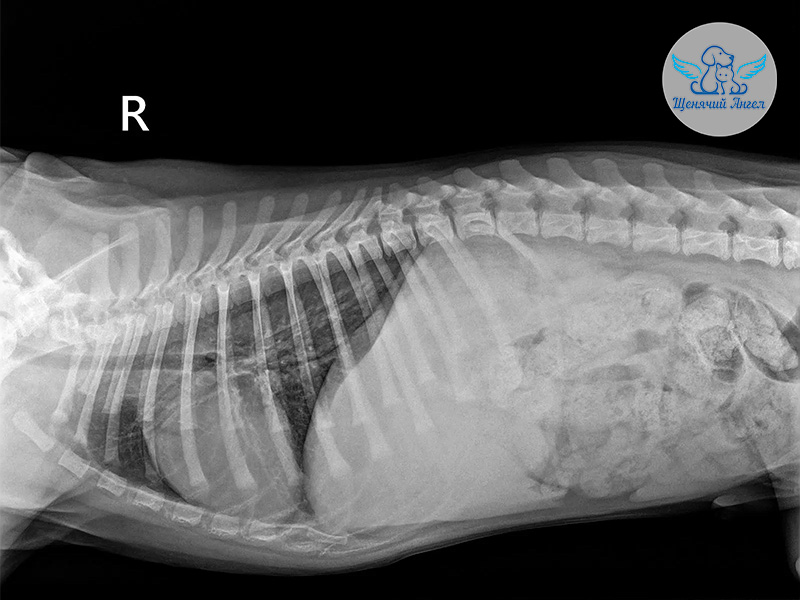

По приезде Джоя доставили в ветеринарную клинику «Джунгли». Врачи провели комплексное обследование и взяли анализы на инфекции 🦠

🩻 Рентген показал перелом голени левой задней лапы. Кроме того, на фоне травмы у Джоя открылось кровотечение в желудочно-кишечном тракте. К счастью, его удалось остановить медикаментозно.

Во время обследования у врачей также возникло подозрение на миокардит – воспаление сердечной мышцы. Дополнительный анализ крови оказался в пределах нормы, однако работу сердца специалисты продолжают внимательно контролировать ☝🏻